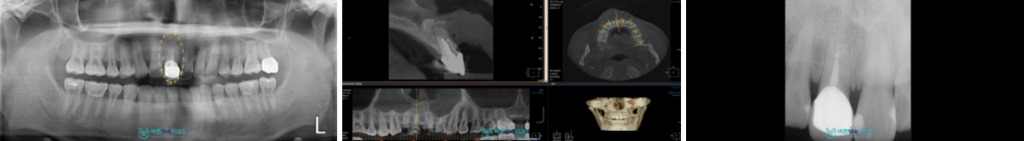

정밀한 검사를 위해

파노라마 사진을 촬영해 보았더니

위턱 오른쪽 첫 번째 앞니(#11)의

뿌리 끝에 염증이 생긴 것을

확인할 수 있었습니다.

예전에 신경치료를 받고

보철물 수복까지 마무리된 치아이지만

현재 뿌리 끝 치근단 부위에

염증이 생긴 것인데요.

더욱더 정밀한 검사를 위해

3D CT 촬영을 통해 염증의 위치와

크기 등을 정확하게 확인하는

과정을 거쳤는데요.